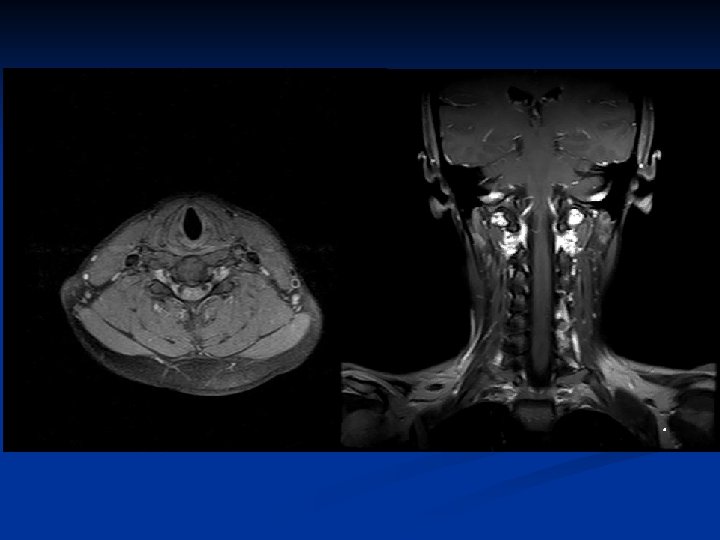

Salivary glands n n Parotid glands Submandibular glands Sublingual glands Minor: tongue, cheeks, lips, palate

Parotid glands The largest of the salivary glands n The duct to this gland (also known as Stensen’s duct) empties within the buccal cavity (the inside of the cheek). n The facial nerve (CNVII) runs through this gland n

Submandibular glands n The Submandibular Gland secretes saliva into ducts called 'Warton's Ducts'. These ducts open on either side of the lingual frenulum.

Sublingual glands n Lie anterior to the submandibular glands under the tongue, beneath the mucous membrane of the floor of the mouth. They are drained by 820 excretory ducts. The largest duct, the sublingual duct (of Bartholin) joins the submandibular duct to drain through the sublingual caruncle.